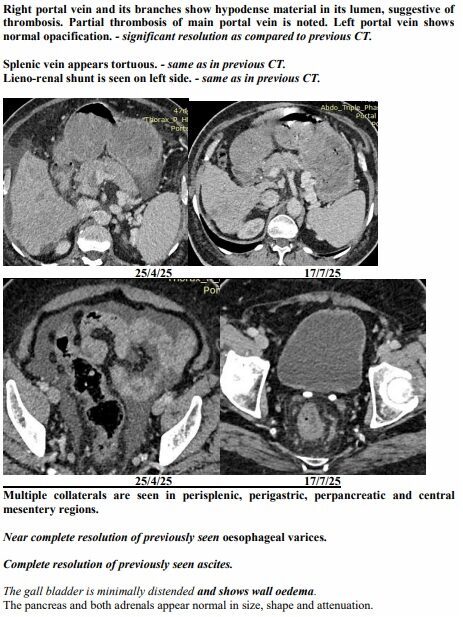

Yet just three months later, on another afternoon in July, the same family stared at a different scan. The tumours had shrunk to one patch. Blood was flowing again. The swelling was gone. Even the alarming tumour marker that had shot up to 1,000 ng/mL had fallen to 10, back in the safe zone. For a man who had been fading fast, it was a turnaround no one in the room dared to predict.

The July scan sealed what they were already feeling at home. The many shadows in his liver had shrunk into one. His abdomen, once swollen with fluid, was flat again. His numbers, which had scared even seasoned oncologists, were suddenly within range.

A senior radiologist who reviewed both reports told this correspondent, “Such a reversal in advanced liver cancer is extremely rare. Clinically, it borders on the unbelievable.”